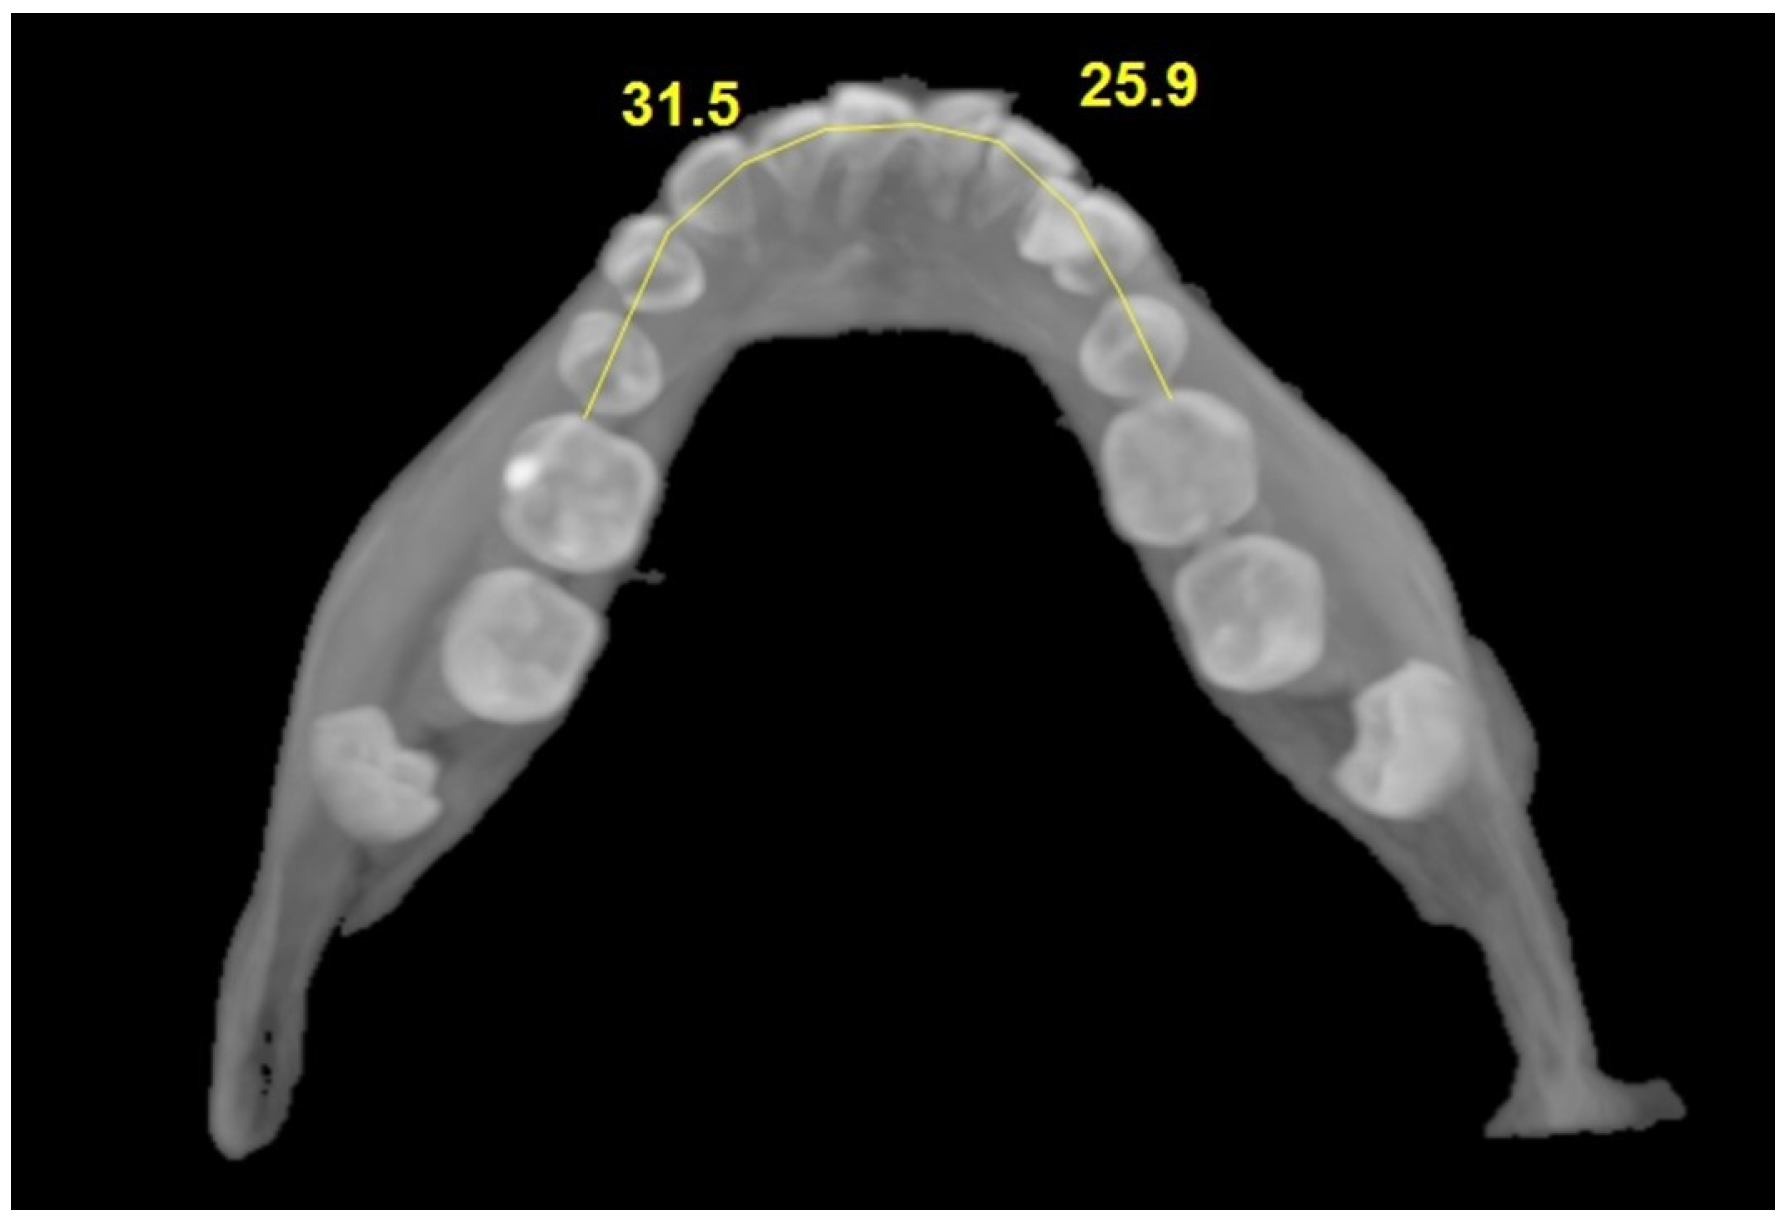

| Impacted Side | Non-Impacted Side | Test Statistic | ||

| Mean ± SD Median (IQR) | Mean ± SD Median (IQR) | z; t | p | |

| Mesiodistal width of the canine | 6.78 ± 0.41 | 6.56 ± 0.40 | t = 2.617 | 0.010 |

| 6.70 (0.50) | 6.60 (0.50) | |||

| Interpremolar width | 15.69 ± 2.29 | 16.45 ± 1.42 | z = 1.864 | 0.062 |

| 16.00 (2.78) | 16.80 (1.65) | |||

| Intermolar width | 21.86 ± 2.27 | 22.44 ± 2.06 | t = 1.393 | 0.166 |

| 22.15 (2.90) | 22.35 (2.80) | |||

| Arch length | 29.92 ± 2.38 | 32.21 ± 2.18 | t = 5.194 | <0.001 |

| 30.05 (2.80) | 32.40 (3.00) | |||